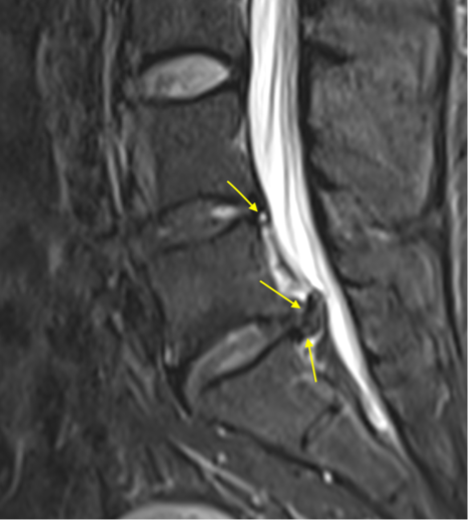

An MRI of the lumbar spine revealed a large L5/S1 disc extrusion in the sub-articular zone that deformed the thecal sac with posterior displacement of the left S1 nerve root (Image 1). An L4/5 central disc protrusion and annular fissure were visualized (Image 2).

(Image 2) Sagittal T2WI

(Image 2) Sagittal T2W